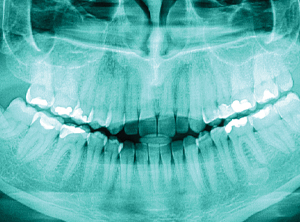

At mydentist, we are proud to offer patients advanced, AI-integrated technologies. These innovations not only enhance the precision and appropriateness of treatments but also provide a more comfortable process and a more predictable outcome for patients.